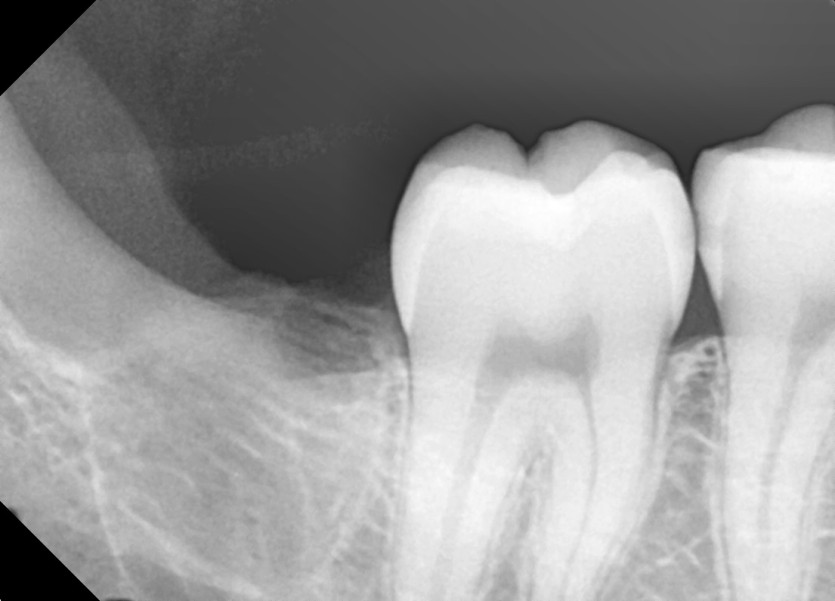

#18,48 사랑니 발치

구강외과 전문의가 당일발치했습니다.